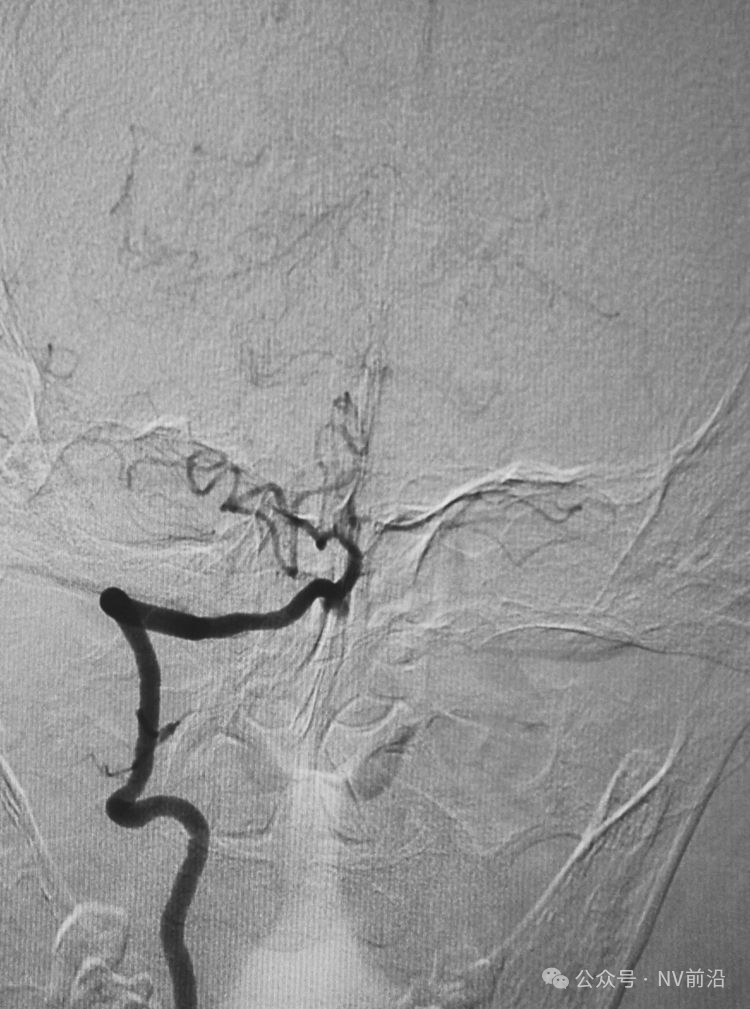

病例一,左侧微小眼动脉瘤,未破裂。

测量:瘤体2.09×2.34 mm,颈宽2.66 mm。

工作位造影

Traxcess 14微导丝可以进入瘤腔,但头端塑成S形的Echelon 10微导管无法跟入。

将微导管在虹吸弯处成襻,越过瘤颈,管头折返钩入瘤腔,即所谓回马枪技术。